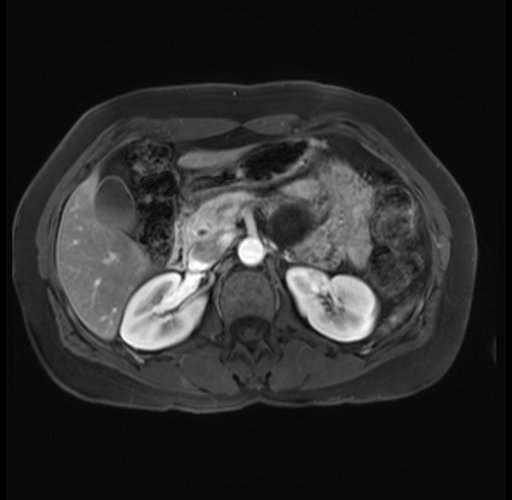

Imaging Analysis

Look through the patient's CT scan to identify any areas of concern for the necessary procedure.

Based on your CT findings, which issue(s) are present and would give reason for "planned slowing down moment(s)" in this case?